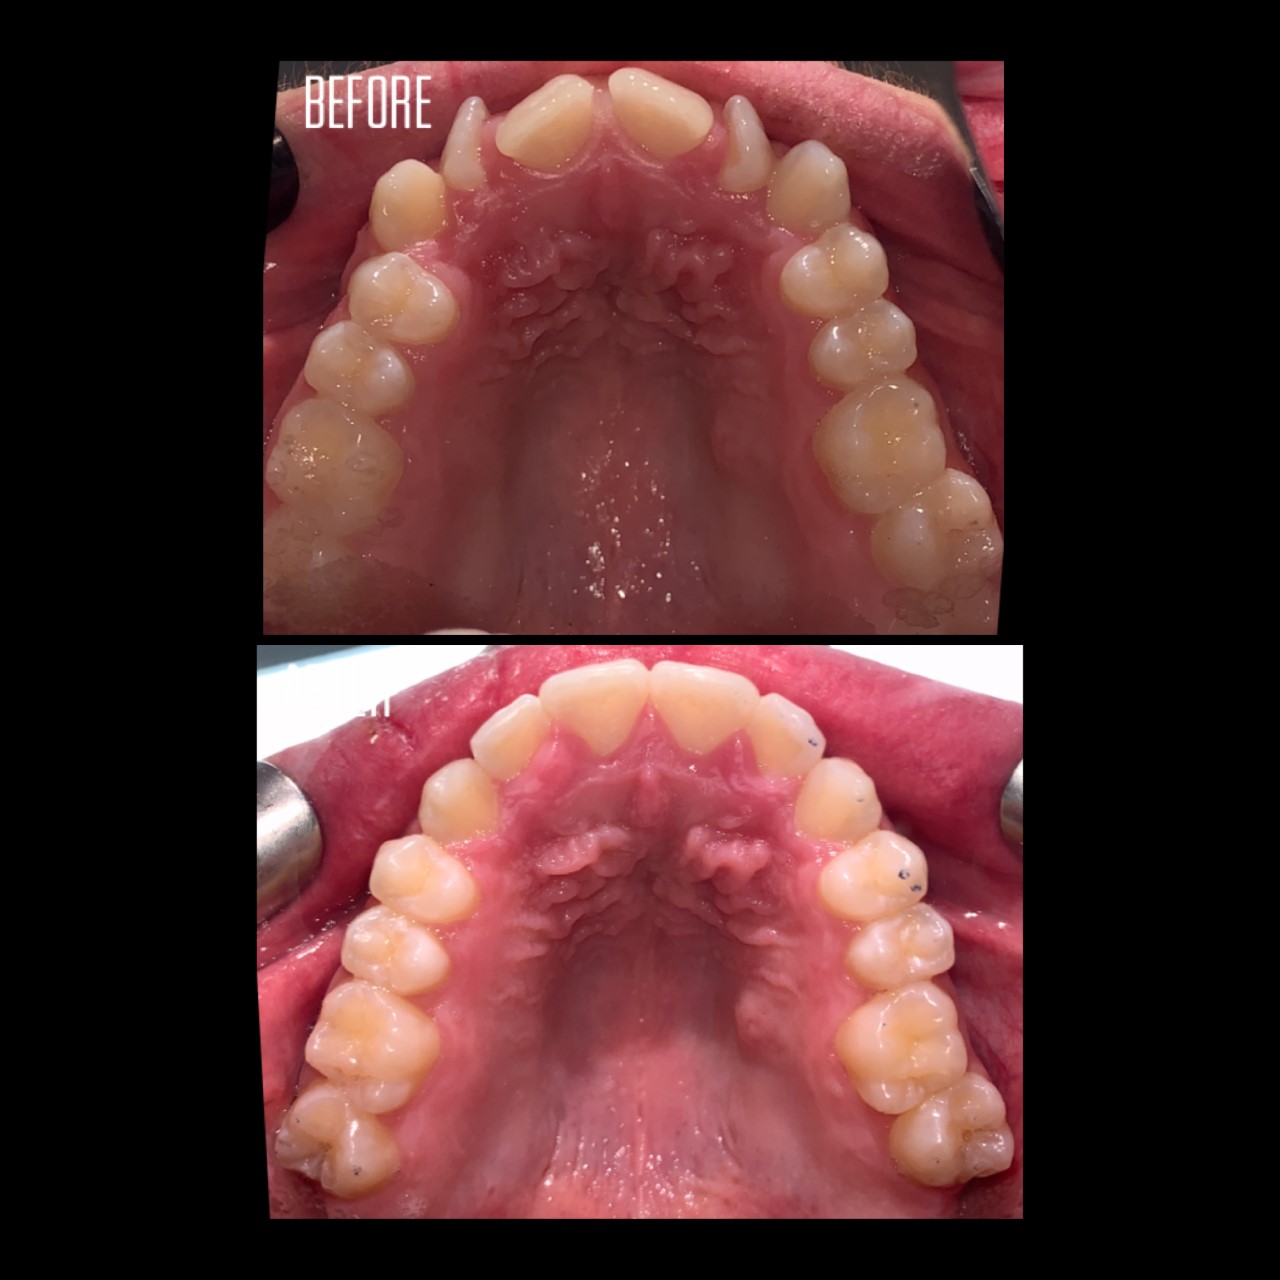

Gallery